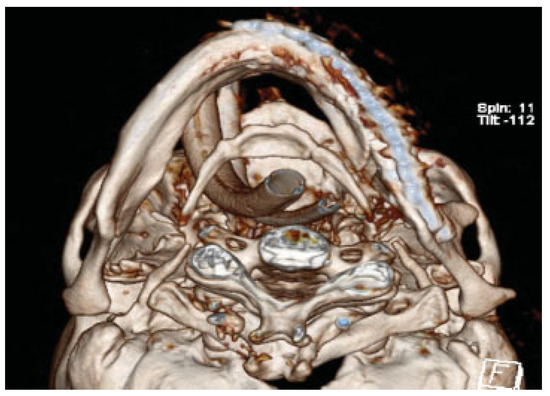

Owing to the significant injury to the anterior and posterior column of the cervical spine, a fusion was performed of C5–T1. Prior to surgery, he was kept in a cervical spine collar. To minimize the time in the operating room (OR) and manipulation of the displaced, atrophic mandible, his initial CT scans were used to fabricate a model to facilitate the correction of the complex mandible fracture. Turnaround time was 5 days. Using three-dimensional (3D) software for VSP (Materialize, Plymouth, MI), the midline of the larger segment of the mandible was aligned with the midline of the maxilla (Figure 2a,b). A mirror image was created using the opposing uninjured mandibular body (Figure 3a,b). A stereo-lithographic model was fabricated facilitating the preoperative bending of a 2.5-mm reconstruction plate, based on the virtually planned model (Figure 4). The plate was contoured to the model the evening before surgery.

Figure 3. (a) A mirror image as seen from frontal. (b) Mirror image as seen from submental vertex.